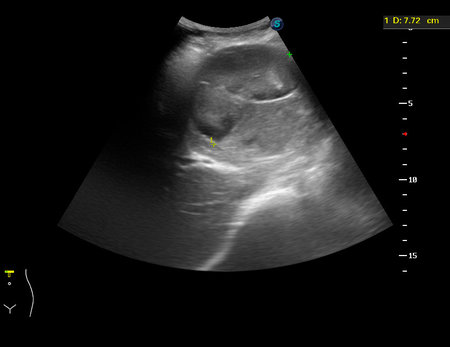

Метастазы ГИСТ в печени. Hepatic GIST Mts

Женщинв 81 год, жалобы на пульсирующее образование в эпигастрии.

С учетом внешнего вида предположена гемангиома больших размеров с разрывом.

Больная прооперирована, выполнена резекция левой доли печени.

Макроскопически - образование на разрезе беловатого цвета, с полостями, заполненными сгустками крови.

Микро: метастаз ГИСТ в печени.